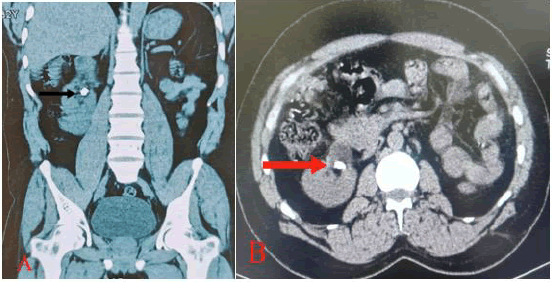

A 32-year-old male patient presented to us in the hospital with chief complaints of right flank pain associated with burning micturition and hematuria. On examination, the patient had moderate tenderness in the right flank region. The patient’s family history was unremarkable. Laboratory investigations and routine urine examination showed a hemoglobin count of 14 g/dl; white blood cell count of 10-12 HPF; Renal function tests showed a creatinine level of 1.0 mg/dl. XRAY KUB showing right renal calculus. (Figure 1A) A Computed Tomography (CT) urogram with contrast showed the right kidney measuring 17 cm in length and an absent left kidney (Figure 2).

Figure 1. (A) Preoperative X-ray KUB revealed stone shadows (arrow) in the right abdominal area. (B) Postoperative KUB showed no stone shadows and arrow show DJ stent.

Figure 2. NCCT KUB (A) and (B) (arrow) showing 1.5 cm calculus in right kidney.